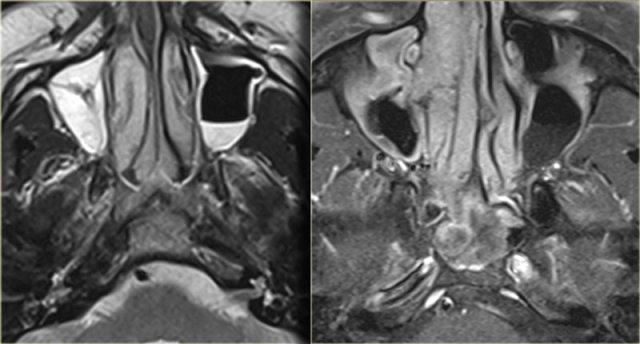

Bên trái là một bệnh nhân khác nhập viện vì nghẹt mũi.

Hãy nghiên cứu các hình ảnh bên trái.

Tự mình xác định xem bạn đang quan sát một khối đặc, dịch tiết cô đặc, sự kết hợp của cả hai, hay một thứ gì đó hoàn toàn khác.

Hình T1W trước tiêm thuốc cho thấy một vùng tăng tín hiệu trong xoang hàm, tương ứng với chất dịch giàu protein.

Phía trong của vùng đó là một vùng giảm tín hiệu tương tự tín hiệu của nhãn cầu (có thể là dạng nang).

Phần lớn mô mềm trong xoang hàm phải tương đối giảm tín hiệu trên hình T1W trước tiêm thuốc,

nhưng ngấm thuốc đồng nhất, gợi ý khối u.

Hình T2W bên trái xác nhận thành phần dạng nang (mũi tên vàng).

Hình CT mặt phẳng coronal minh họa rõ nét hình ảnh tái cấu trúc xương và giãn nở (đầu mũi tên).

Kết quả giải phẫu bệnh xác nhận là u nhú đảo ngược.

Vị trí tổn thương khá điển hình.